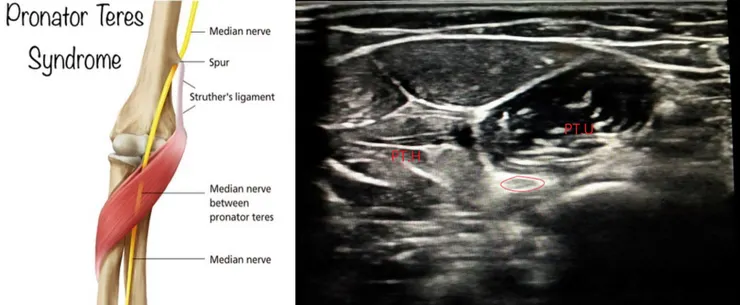

正中神經如果不在腕隧道被壓到,在上游一點也可以在壓到,被旋前圓肌(Pronator teres)壓到,旋前圓肌症候群(Pronator teres syndrome)跟腕隧道症候群在臨床上很難區分,但是肌肉神經電學可以區分。超音波一樣能看到正中神經遊走於旋前圓肌的兩頭(尺骨頭與肱骨頭)之間。